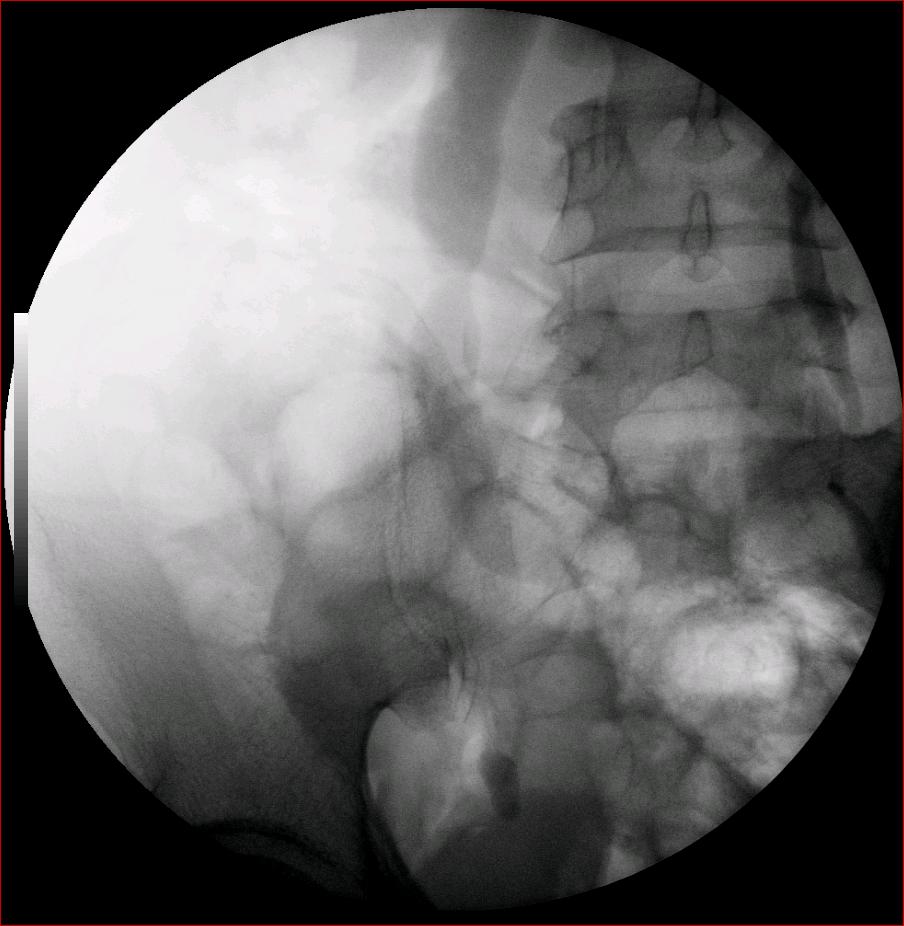

以下是引用luoxinjun在2008-2-18 15:54:00的发言:[br]右肾积水,右输尿管下端结石

以下是引用zhangxiangjun在2008-2-18 21:01:00的发言:[br]右输尿管盆段末端结石,继发其近端输尿管、右肾积水。

以下是引用hexue在2008-2-18 17:33:00的发言:[br]右输尿管下段结石并右肾及右输尿管积水扩张

以下是引用杀毒软件在2008-2-18 16:24:00的发言:[br]右输尿管下段结石,肾盂积水。